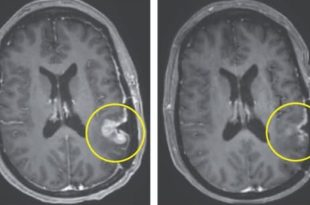

মাত্র এক ডোজ পরীক্ষামূলক ওষুধ প্রয়োগের পর এক নারীর মস্তিষ্কে থাকা মারাত্মক টিউমার মাত্র পাঁচ দিনের মধ্যেই প্রায় সম্পূর্ণ অদৃশ্য হয়ে গেছে! যুক্তরাষ্ট্রের ম্যাসাচুসেটস জেনারেল ক্যান্সার সেন্টারে পরিচালিত এক যুগান্তকারী ক্লিনিক্যাল ট্রায়ালে এই চমকপ্রদ সাফল্য অর্জিত হয়েছে। বিজ্ঞানীরা বলছেন, এটি …